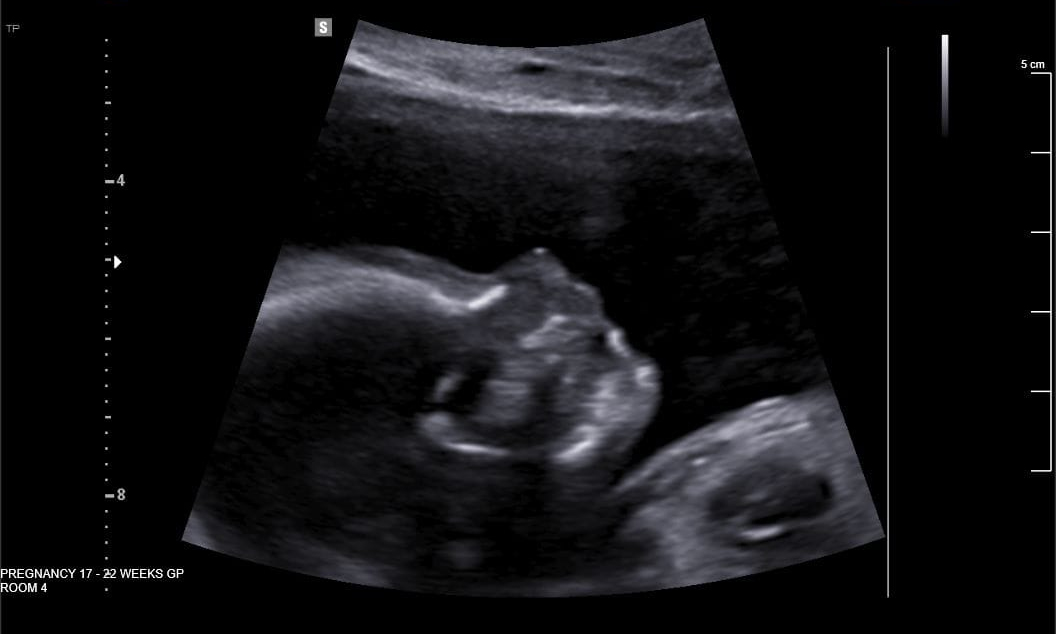

We’re about to be joined on our adventures by a new arrival and I couldn’t be more excited!! I can’t wait to meet this tiny human and bring them along on our journeys into the bush. They’ve already been to more places while in the womb than many people have been their whole lives and I’m sure they won’t be at all pleased when we tell them they were in Iceland but didn’t get to see anything!

The pregnancy has of course curtailed our more extreme adventures and made the big trip to Ireland, Iceland and Hong Kong a little different than we had planned. Poor Gemma didn’t get to get smashed at an Irish wedding for starters haha!